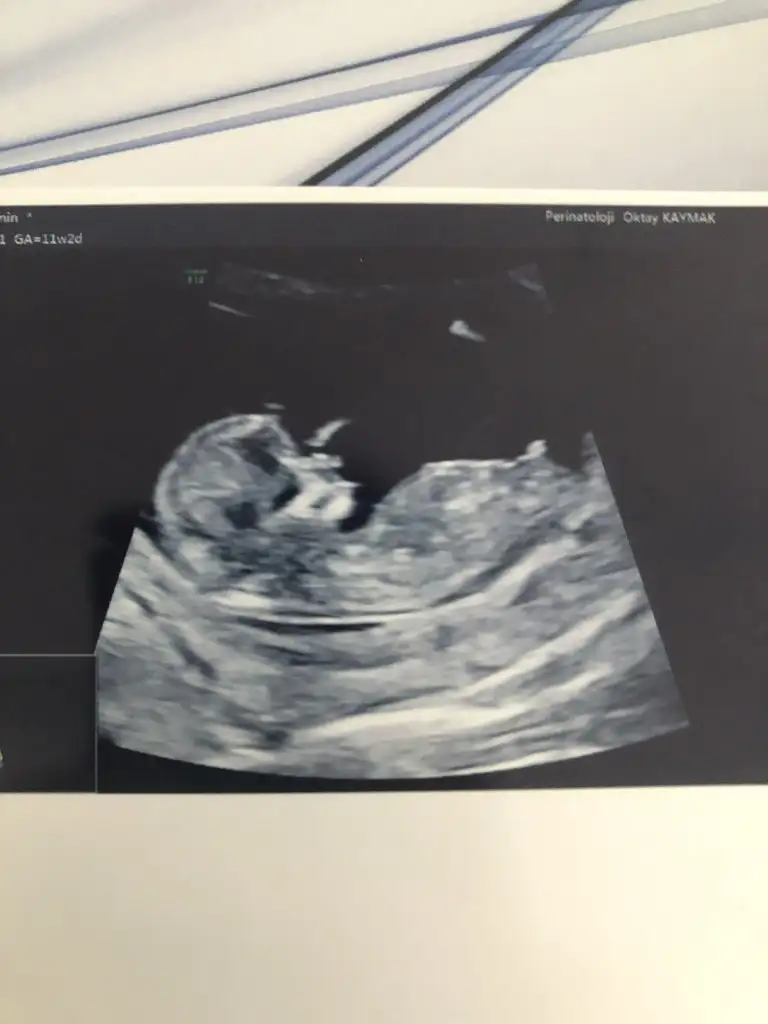

Hadi gozun aydin insaAllah bana da bisi yok der ve testi yaptirmayi dusunmuyorum.Cinsiyet de belli olmus hayirla gelsin insaAllah. Ultrason resmi var mi?

İnsallah hepimizinki 🥰 doktor ozellikle cekti bu resmi 😂

Kizlar bugun perinatologa gittim detayli ultrasonda ölçtü Bebegin tum organlarini bir sorun yok dedi.gayet saglikli gorunuyormus icin rahat olsun dedi.nifty test ve ikili test icinde eger bir sorun cikarsa duzeltmek icin mudahele edilemezmis sadece riskli yada degil diyebilirmis.bende yaptirmadim test .sizce yanlis mi yaptim .yaptirmalimiydim.Birde cinsiyetini ogrendik net erkek 😀